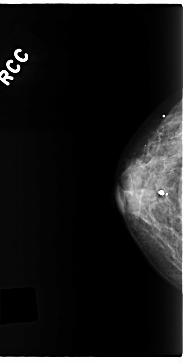

C_0221_1.RIGHT_CC

RIGHT_CC LINES 4696 PIXELS_PER_LINE 2376 BITS_PER_PIXEL 12 RESOLUTION 50 NON_OVERLAY